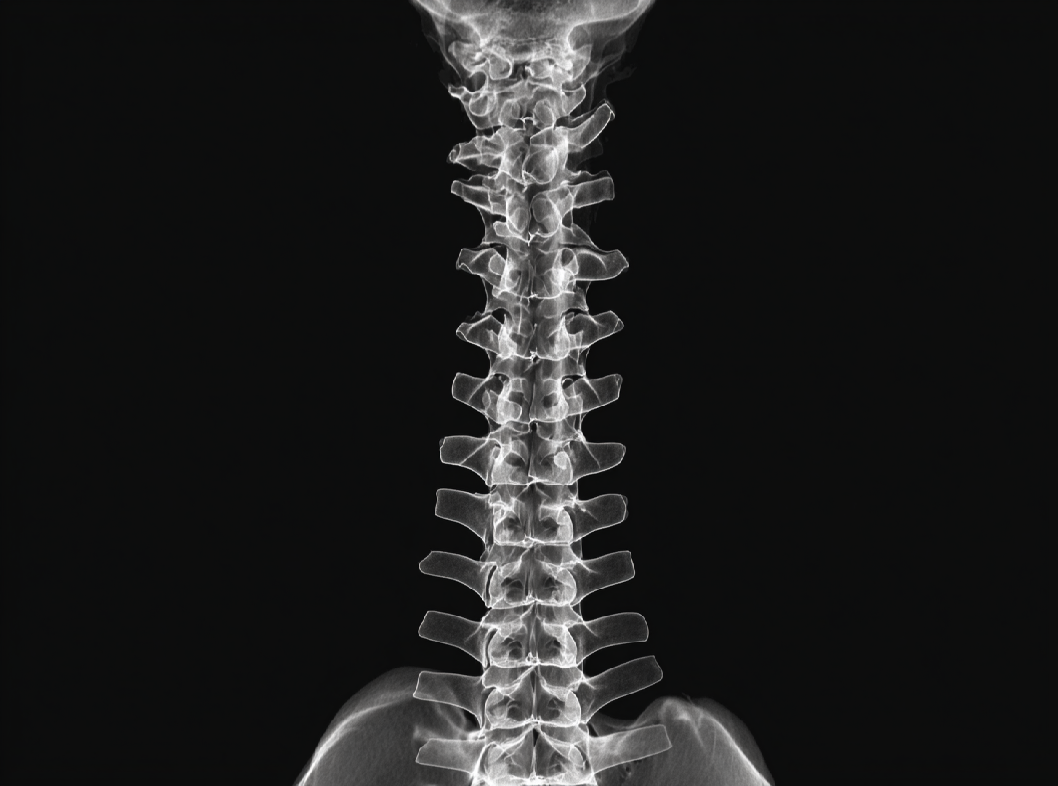

Диагностика искривления позвоночника включает в себя различные методы исследования для определения типа и степени искривления, а также оценки возможных симптомов и последствий. Вот некоторые общие методы диагностики:

Врач проведет внимательное физическое обследование, включая визуальную оценку позвоночника в покое и при движении. Врач также может проверить равномерность плеч, лопаток и таза. Измерение углов искривления. С помощью рентгеновских снимков спины в различных проекциях врач может измерить углы искривления и определить тип сколиоза, кифоза или лордоза. Магнитно-резонансная томография МРТ может предоставить более детальные изображения мягких тканей, нервов и дисков между позвонками, что может быть полезно при диагностике. Компьютерная томография КТ-сканирование предоставляет более подробные изображения костей и структур позвоночника.